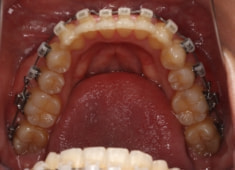

治療開始から24ヶ月後